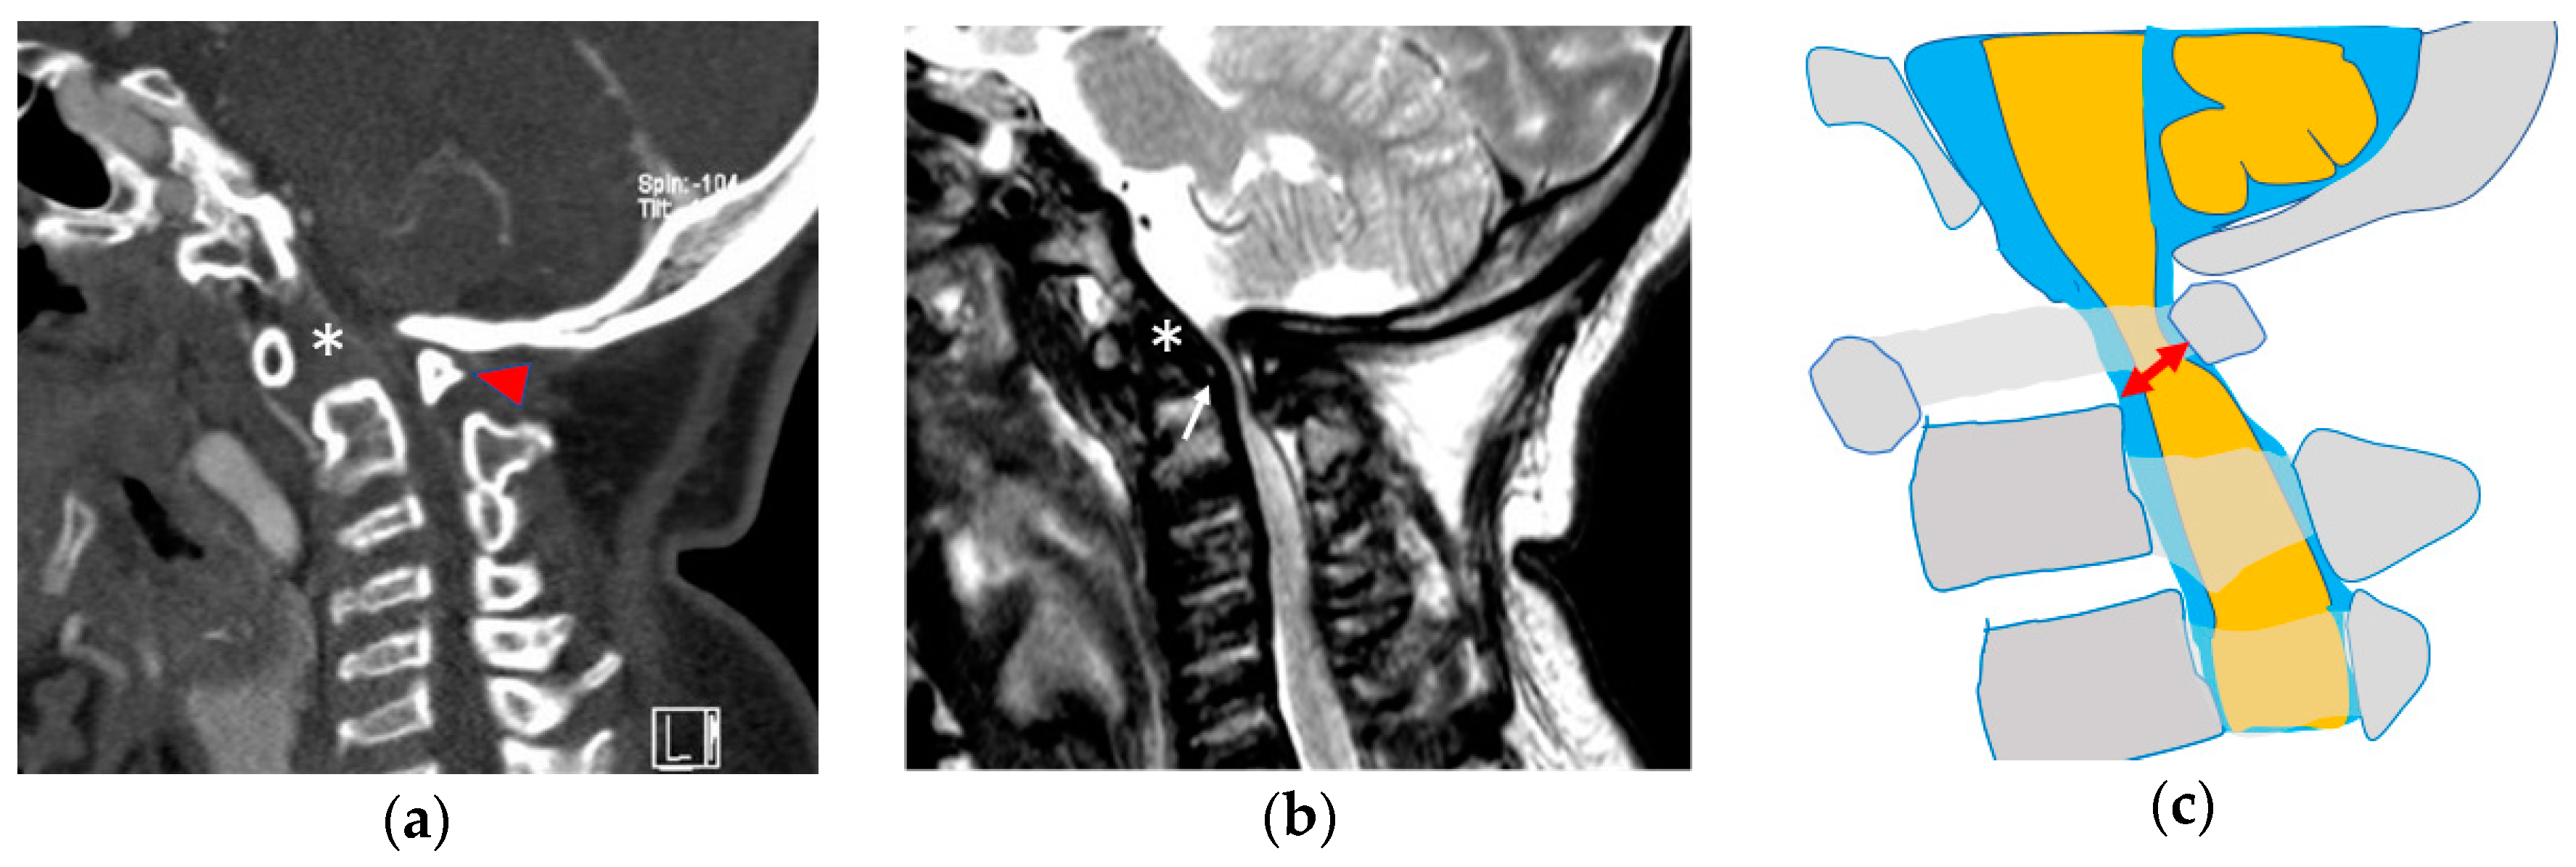

2.1.1. Atlantoaxial Instability

2.1.2. Cervical Stenosis